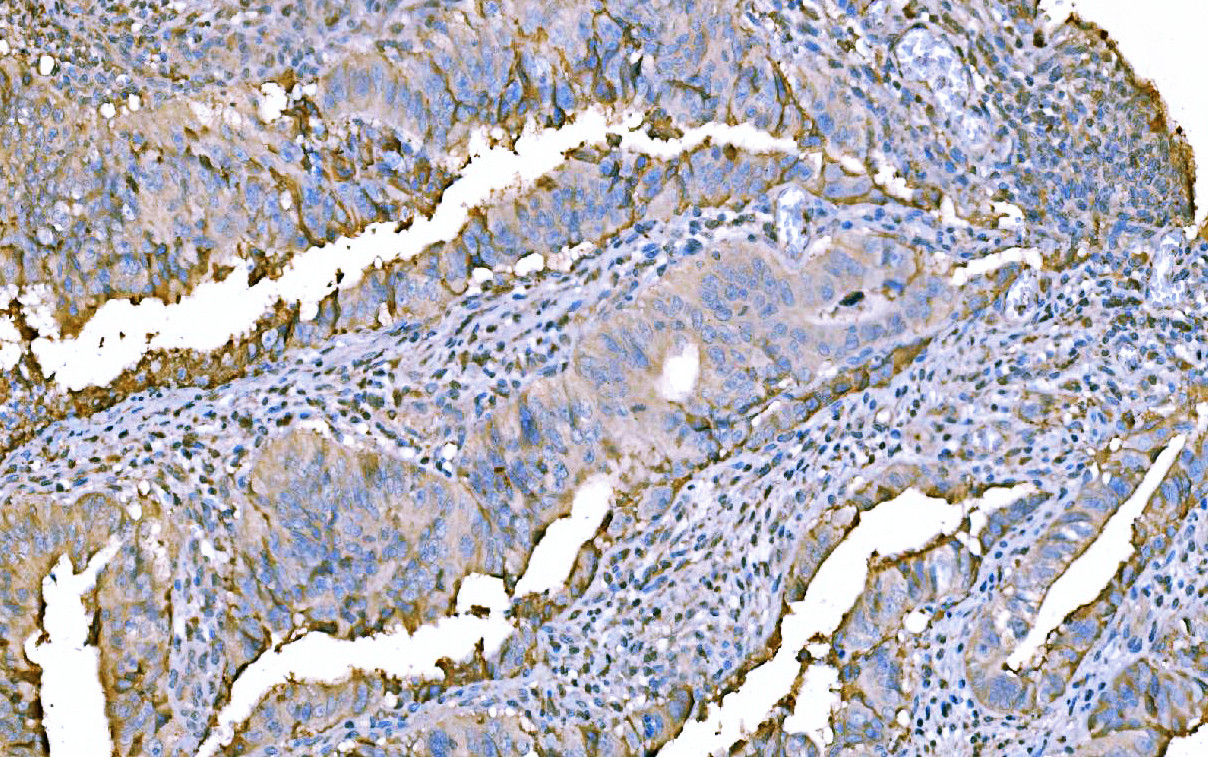

IHC analysis of F2 using anti-F2 antibody (M00044-2).

F2 was detected in a paraffin-embedded section of human Colorectal cancer tissue. Biotinylated goat anti-mouse IgG was used as secondary antibody. The tissue section was incubated with mouse anti-F2 Antibody (M00044-2) at a dilution of 1:200 and developed using Strepavidin-Biotin-Complex (SABC) (Catalog # SA1021) with DAB (Catalog # AR1027) as the chromogen.